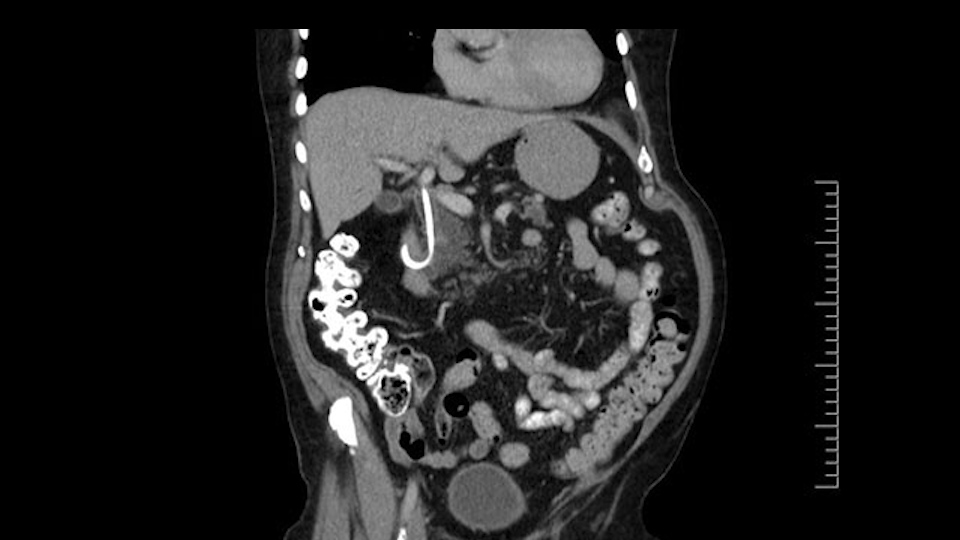

The other thing I look at is the gastroepeiploic arcade- which is this thing here- which is where the gastroepeiploic vein joins the portal vein. I call it the gateway to the neck of the pancreas because you pretty much have to divide it to get to the neck. The middle colic vein usually drains either into it or nearby. I think we’re seeing it here. Again,that can be divided and I usually divide those two and it helps me get under the neck. Again, there’s no issues here with the tumor so it’s nice from that perspective. If I was concerned about the vein, which I’m not here, I would go to the coronal view. It’s a nice way to look at the vein on just a couple of cuts and you can see a beautiful view of it here. There’s the portal vein, there’s the head of the pancreas. There’s the tumor. It’s a little closer here than it looks on the other one. I doubt it’s involved. If it’s touching, it may not be invading it but even if it was, it's a short segment. Anyways, there’s the SMV there’s the splenic vein, and everything looks good. You can see the stent. I ignore the stent. It’s the most dramatic looking thing in the picture but it’s actually the least important.

The next thing we always evaluate, although we do not expect invasion to the portal veins in this case, we must always trace the path of the portal vein, in both directions, from top to bottom. The splenoportal confluence and the superior mesenteric vein, which in this case does not appear to be compromised.

Por otro lado, siempre evaluamos -aunque en este caso no esperamos que haya invasión de los vasos portales-, siempre hay que hacer el recorrido de la vena porta, en ambos sentidos, de arriba hacia abajo; el confluente esplenoportal y la vena mesentérica superior, que en este caso no aparentan estar comprometidos.